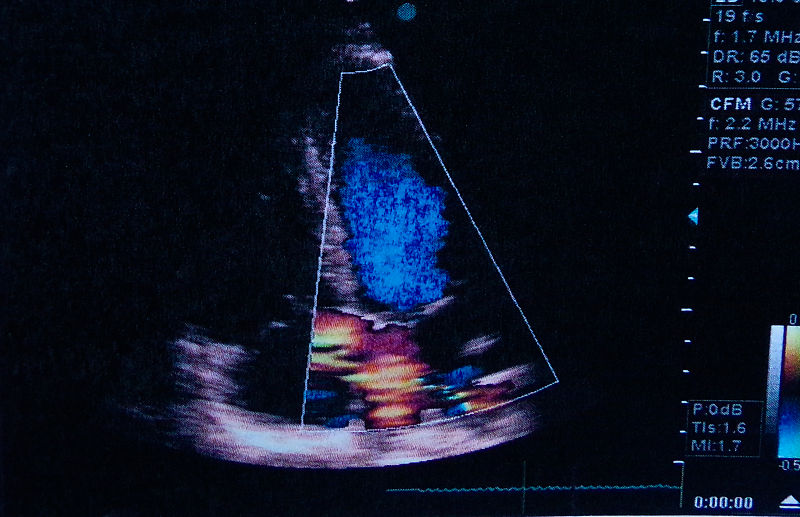

三、心房纤颤 。

这是老年人常见的一种心律失常 。 早期多是间歇性发作 , 最后往往转为持续性 。 心房纤颤的病因 , 大多是由冠心病、高血压心脏病引起 。

心房纤颤的特点是:①每分钟心跳次数和脉跳次数不一致、而且心跳次数多于脉跳次数 。 ②心脏跳动不规则 , 时强时弱 , 时快时慢 。 老年人如果出现心房纤颤 , 应当及时去医院检查治疗 。